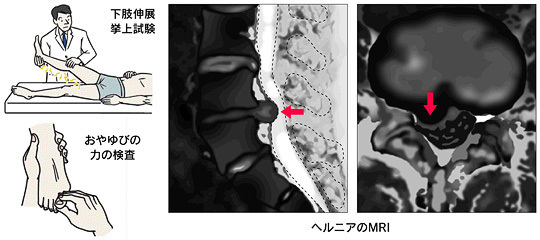

下肢伸展挙上試験(SLRテスト、ラセーグテスト)・・・

膝を伸ばしたまま下肢を上げ、坐骨神経痛の出現を見ます。

下肢の感覚が鈍いかどうか、足の力が弱くなっていないか等で診断します。

さらに、X線(レントゲン)撮影、MRIなどで検査を行い診断を確定します。

MRI画像で椎間板が突出していても、症状が無ければ多くの場合問題はありません。